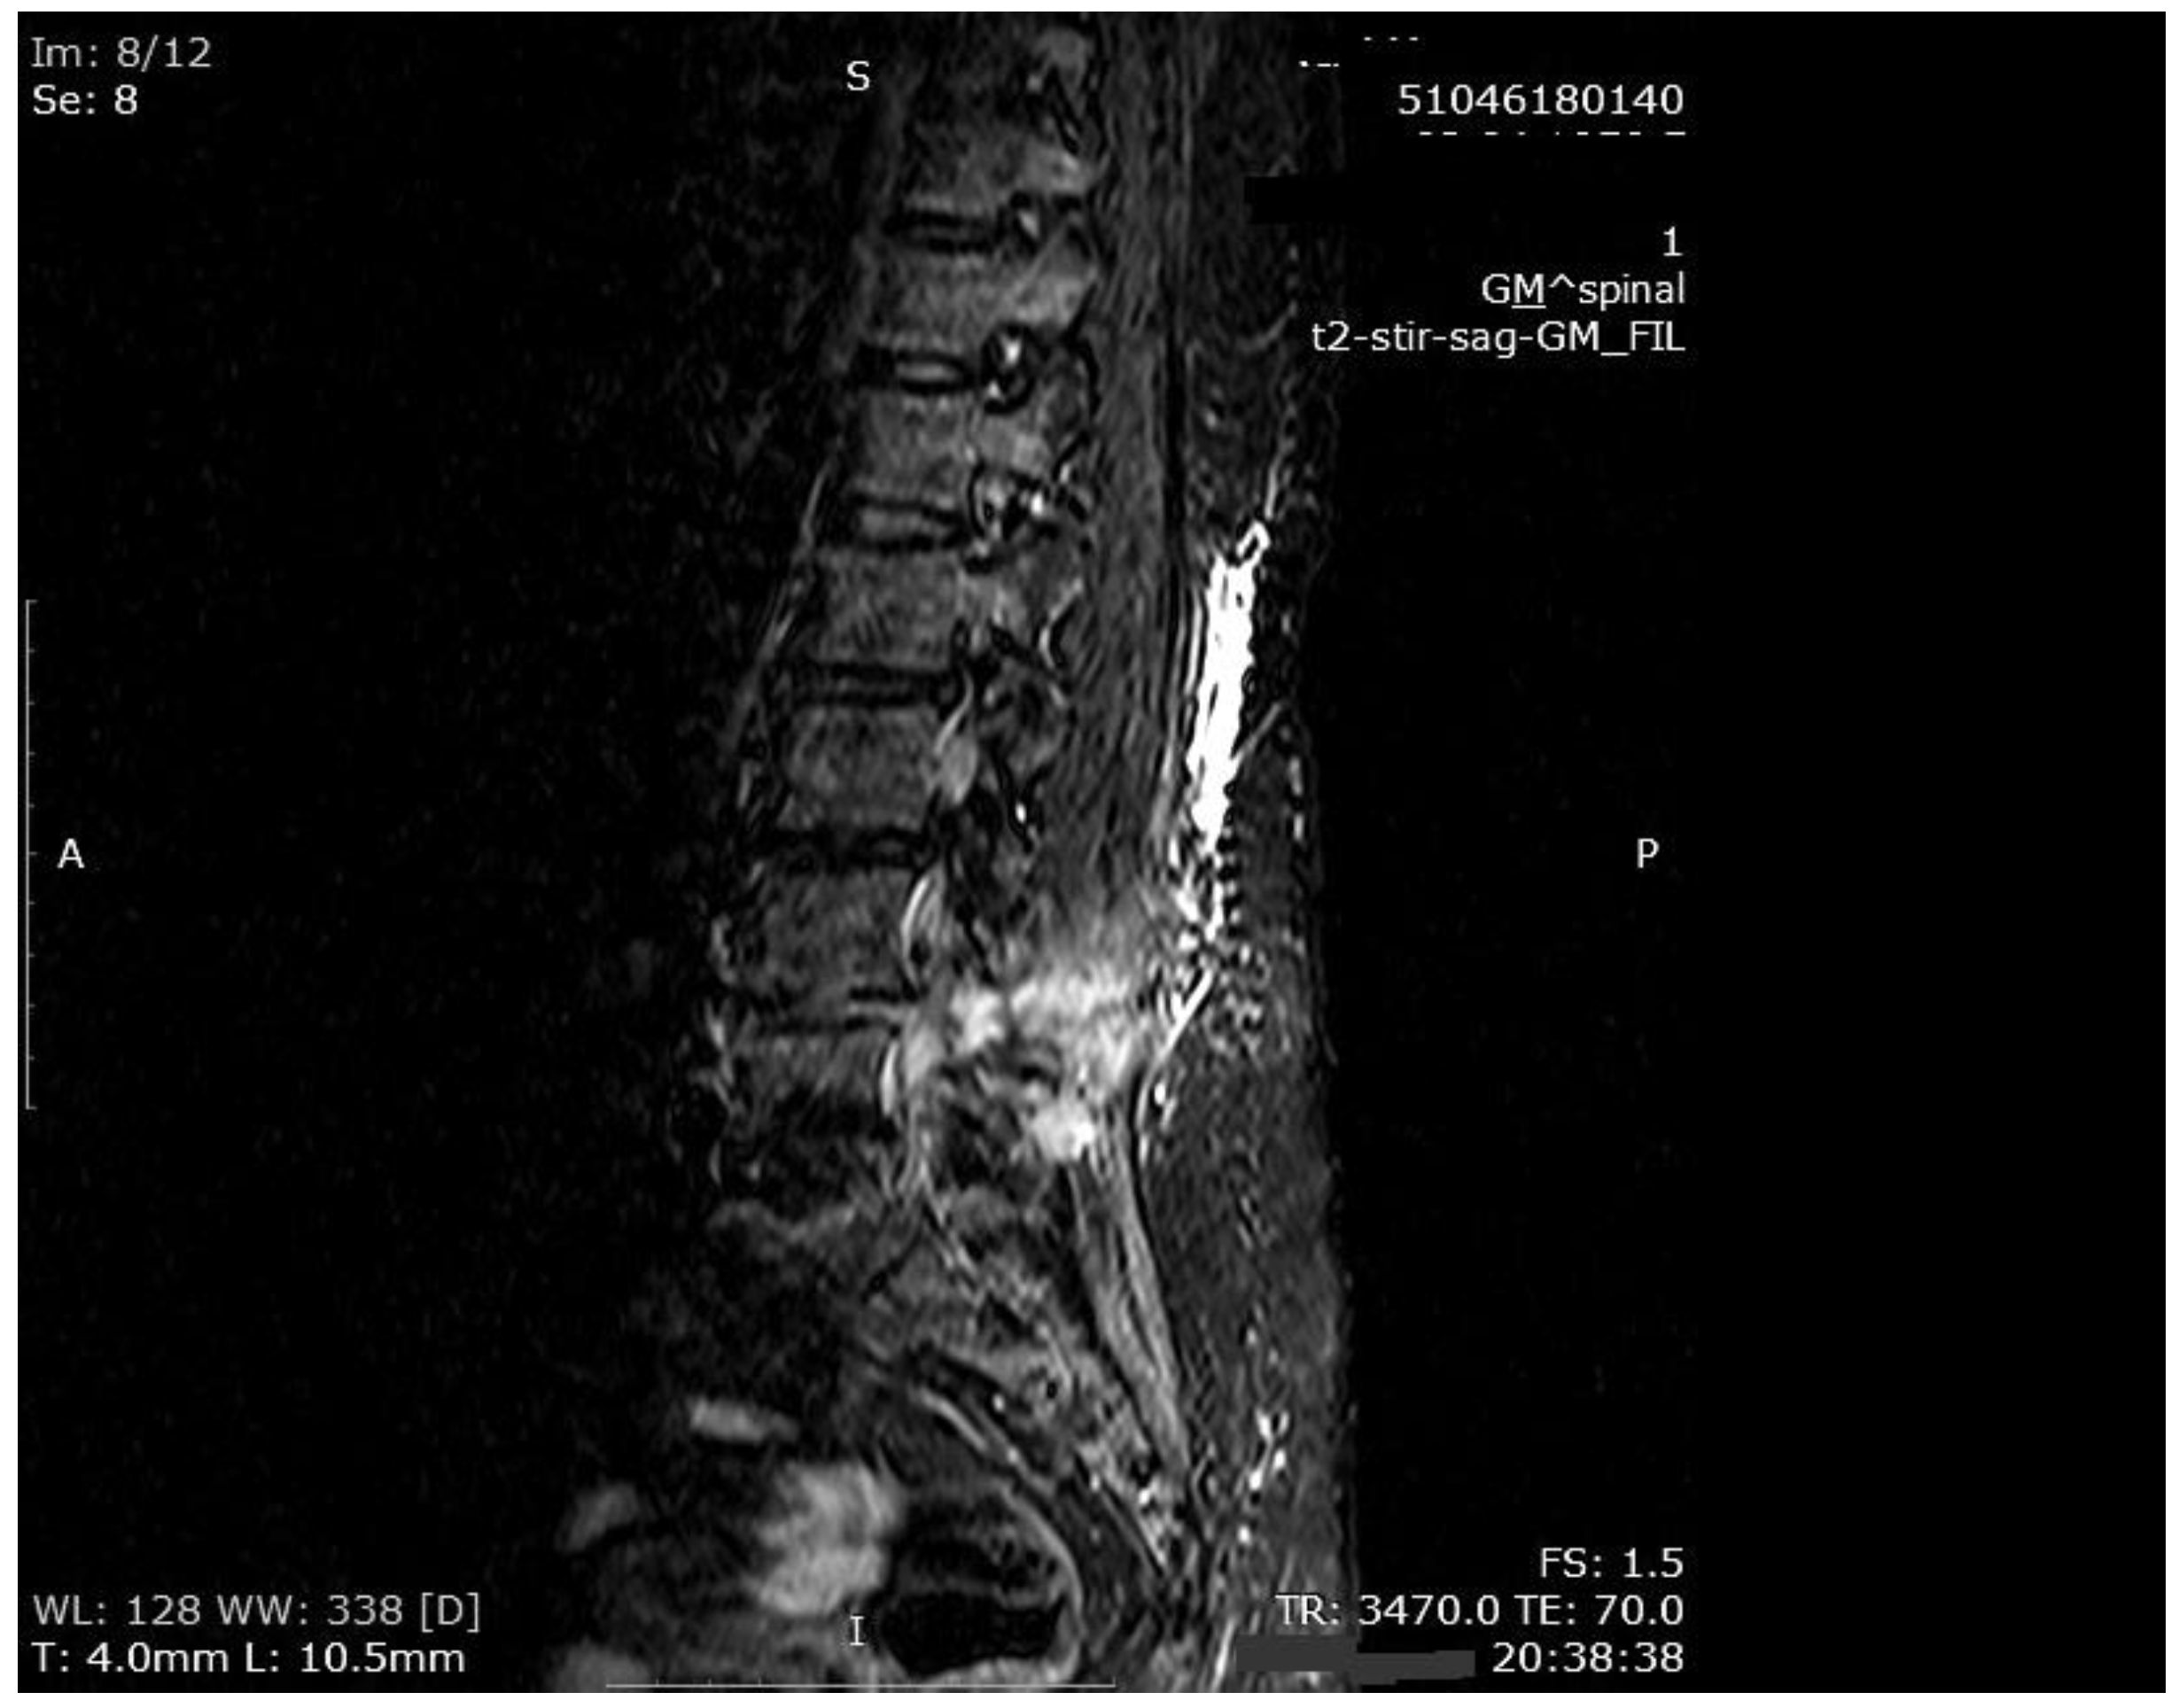

Figure 4. MR imaging T2-weighted scan showing inflammatory infiltrates in the course of pre-HBO2 treatment.

The mean number of total HBO2 sessions was 33 (±18.5) sessions. The HBO2 treatment was tolerated well by all patients except two. One patient had to receive analgesics (non-steroidal anti-inflammatories) before HBO2 sessions because she had severe back pain, and in one patient the treatment was interrupted for five days because of minor middle ear barotrauma. Improvements in clinical evaluations and laboratory findings were observed in all cases at the end of the HBO2 therapy. The mean erythrocyte sedimentation rate (ESR) value reduced from 76.1 (range, 6–129) to 45.7 (range, 5–81) mm/h, and the mean C-reactive protein (CRP) concentration reduced from 82.9 (range, 14–202) to 17.5 (range, 1–49.5) mg/L (normal limits; ESR: <20 mm/h, CRP: 0–5 mg/L). Infection resolution was adequately achieved in 12 of 13 patients on MR imaging at the end of HBO2 treatment or during the first month of follow-up (Figure 3, Figure 4 and Figure 5). There was no significant improvement in one patient. To extend the total clinical follow-up period up to three years (mean: 11 months; range, 1 month–3 years), telephone interviews were conducted to determine any recurrence of symptomatic clinical infection. No recurrence of infection, spinal instability, or deformity was seen in any patients.